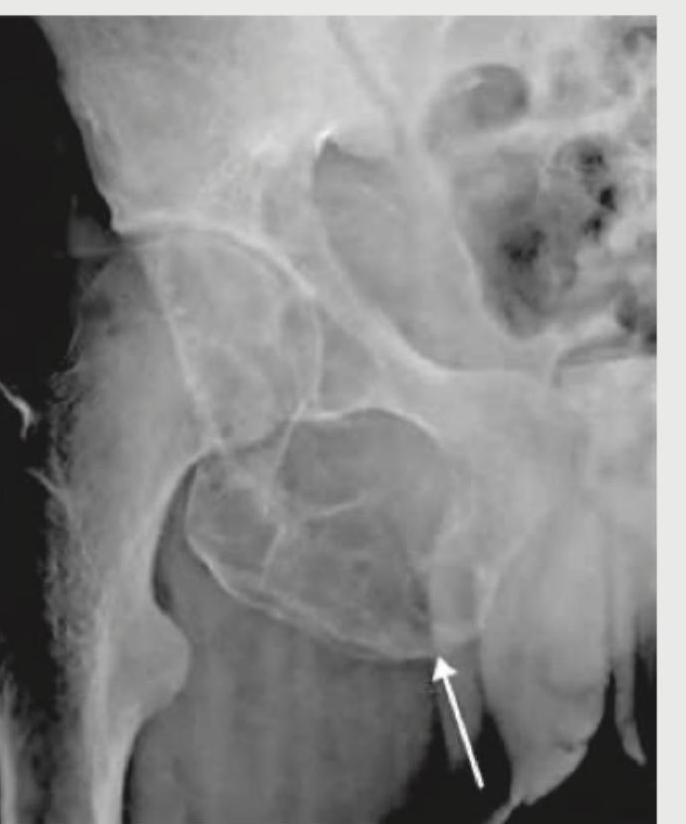

The following X-ray of the pelvis shows:

Explanation: ***Gas shadow artifact*** - The image shows a **dark, lucent area (gas shadow)** overlying the pelvic structures, particularly noticeable over the soft tissues and potentially obscuring parts of the bone. This indicates extraneous gas, likely from the bowel, that is projected onto the image. - Artefacts like gas shadows are common in X-rays and can sometimes mimic or obscure pathology, but their characteristic appearance helps differentiate them from true bone lesions or dislocations. This is an artifact. *Simple bone cyst* - A simple bone cyst (also known as a **unicameral bone cyst**) typically appears as a well-defined, lytic lesion with a sclerotic rim within the bone, often associated with a "fallen fragment sign" if a fracture has occurred. - The appearance in the image is not consistent with a true bone lesion within the bone itself but rather an overlying shadow. *Aneurysmal bone cyst* - An aneurysmal bone cyst is an expansile, lytic lesion that often presents with a **"soap bubble" appearance** and may contain fluid-fluid levels on MRI. - This lesion is typically intraosseous and causes bone expansion, which is not depicted by the observed gas shadow. *Posterior hip dislocation* - A posterior hip dislocation involves the **femoral head being displaced posteriorly and superiorly** relative to the acetabulum, leading to characteristic changes in the hip joint alignment. - The image does not show a change in the anatomical relationship between the femoral head and acetabulum; instead, it shows an external lucency.